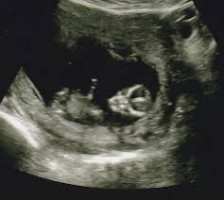

Matti ja Maija ovat saamassa lapsen. Sikiöseulonnassa kuitenkin selviää, että sikiöllä on kromosomipoikkeavuus. Tulisiko vanhempien päättää raskaus?